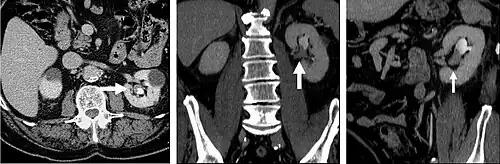

Plain CT urography (without contrast) is used to evaluate stone diseases, calcifications within kidneys, density of renal masses and presence of any bleeding before contrast is given. Then iodinated contrast is given intravenously to evaluate kidney tumours (if any) and urinary tract. CT scan is then taken at 30 to 70 seconds (when the contrast reaches the renal cortex and renal medulla) to evaluate the perfusion and vascularity of the kidneys. CT scan taken at 90 to 180 seconds (when the contrast perfused the whole kidney) to evaluate the characteristics of kidney masses. The contrast starts to drain into the collecting system of the kidneys at 3 minutes after injection and the whole collecting system is well distended with contrast at 8 to 10 minutes. Taking a CT scan at this time is useful to evaluate any strictures or masses from within the ureters or from outside but compressing on the ureters.[2] Contrast CT urography is also useful to monitor whether a tumour is responding to treatment.[3][4]

CT urography (CTU) is commonly used in the evaluation of hematuria, and specifically tailored to image the renal collecting system, ureters and bladder in addition to the renal parenchyma.

The CT scan will image the urinary tract, including the kidney, ureters, bladder, and urethra.[3] It does this by taking many cross-sectional images that can be computationally arranged so as to provide 3D information.[3] The scan itself usually involves a CT scan without contrast (a non-contrast phase), a CT scan while the contrast is within the kidneys (a parenchymal phase), and a CT scan taken while the contrast travels through the renal tract (an excretory phase).[4]